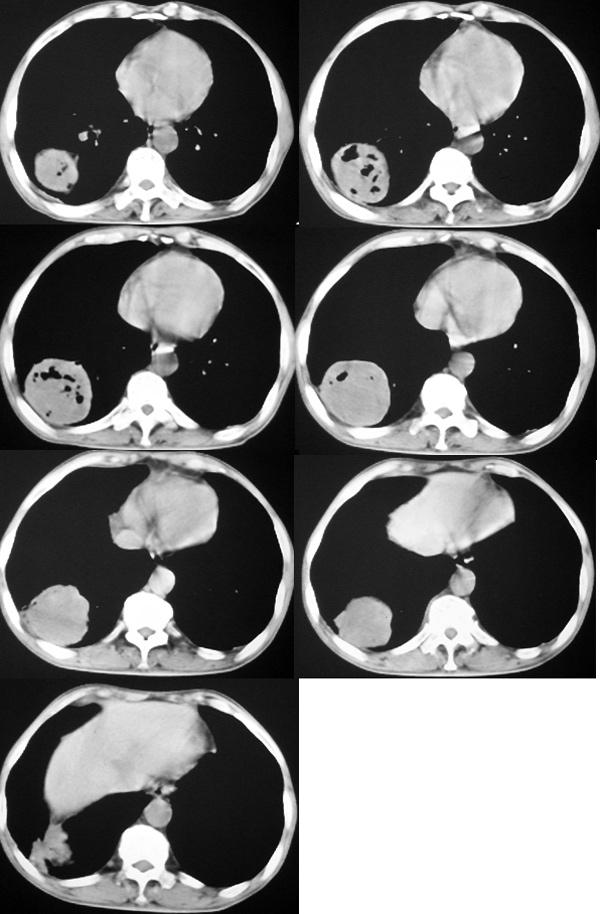

我认为本例肿块内为坏死组织与实性组织混在一起,并夹杂有极低密度气体影,加上肺肿边缘部分呈不规则浅分叶,应该诊断为周围型肺癌。

患者三个月前的ct增强片也显示肿块壁不规则并有明确的壁结节,也支持周围型肺癌的诊断。

如果患者仅是单纯的慢性肺脓疡,在经历了三个多月的治疗后,其内的坏死液化组织与气体应该形形一些短的气-液平面,而本例肿块内没有一个典型的气-液平面。

2008年8月19日ct所见为实性肿物,轻度强化,而患者仅有“胸闷、食欲不振”的症状,没有发热病史,因此考虑良性肺肿瘤可能性大。

本次ct检查,在肿块内出现了气体,而且“近期始终间断性发高烧”,考虑肿瘤合并感染可能性。

感谢楼主反馈结果。囊实性肿块,壁厚薄不均,壁结节有明显强化,均支持肺癌诊断。